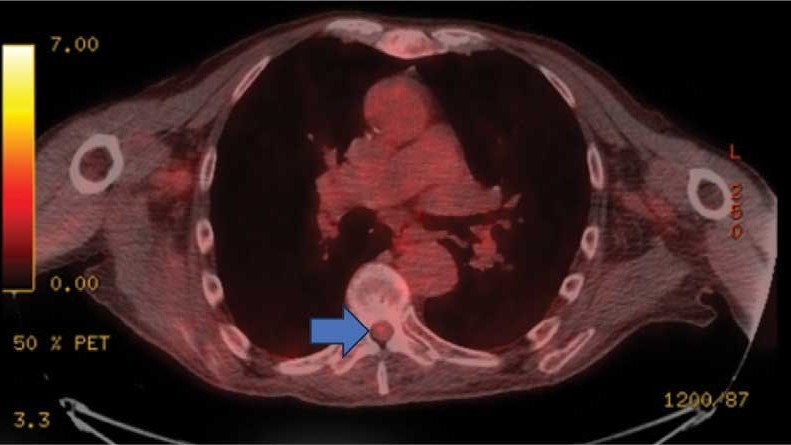

This patient presented with progressive right-sided lower extremity weakness and hypoesthesia and a history of a low-grade right renal/pelvic ureteral tumor. The immediate impression was that the thoracic intramedullary lesion represented a metastatic lesion. However, in the absence of any systemic or intracranial metastases, this progression was much less likely. An extensive interdisciplinary workup was conducted that included medical oncology, neurology, neuroradiology, neuro-oncology, neurosurgery, nuclear medicine, and radiation oncology. Neuroradiology and nuclear medicine identified a slightly hypermetabolic focus on the PET/CT from 1.5 years prior that correlated exactly with the same location as the lesion on the recent spinal MRI. This finding, along with the MRA, confirmed the diagnosis of a dAVF, which was successfully managed conservatively with dexamethasone and physical therapy, rather than through oncologic treatments such as radiotherapy

This case demonstrates the importance of an interdisciplinary workup when evaluating an intramedullary lesion, as well as maintaining a wide differential diagnosis, particularly in the absence of a history of polymetastatic cancer. All the clues (such as the slightly hypermetabolic focus on a PET/CT from 1.5 years prior) need to be obtained to comfortably reach a diagnosis in the absence of pathologic confirmation. These cases can be especially challenging due to the lack of pathologic confirmation, but by understanding the main differentiating features among the various etiologies and obtaining all available information, a correct diagnosis can be made without unnecessary interventions.